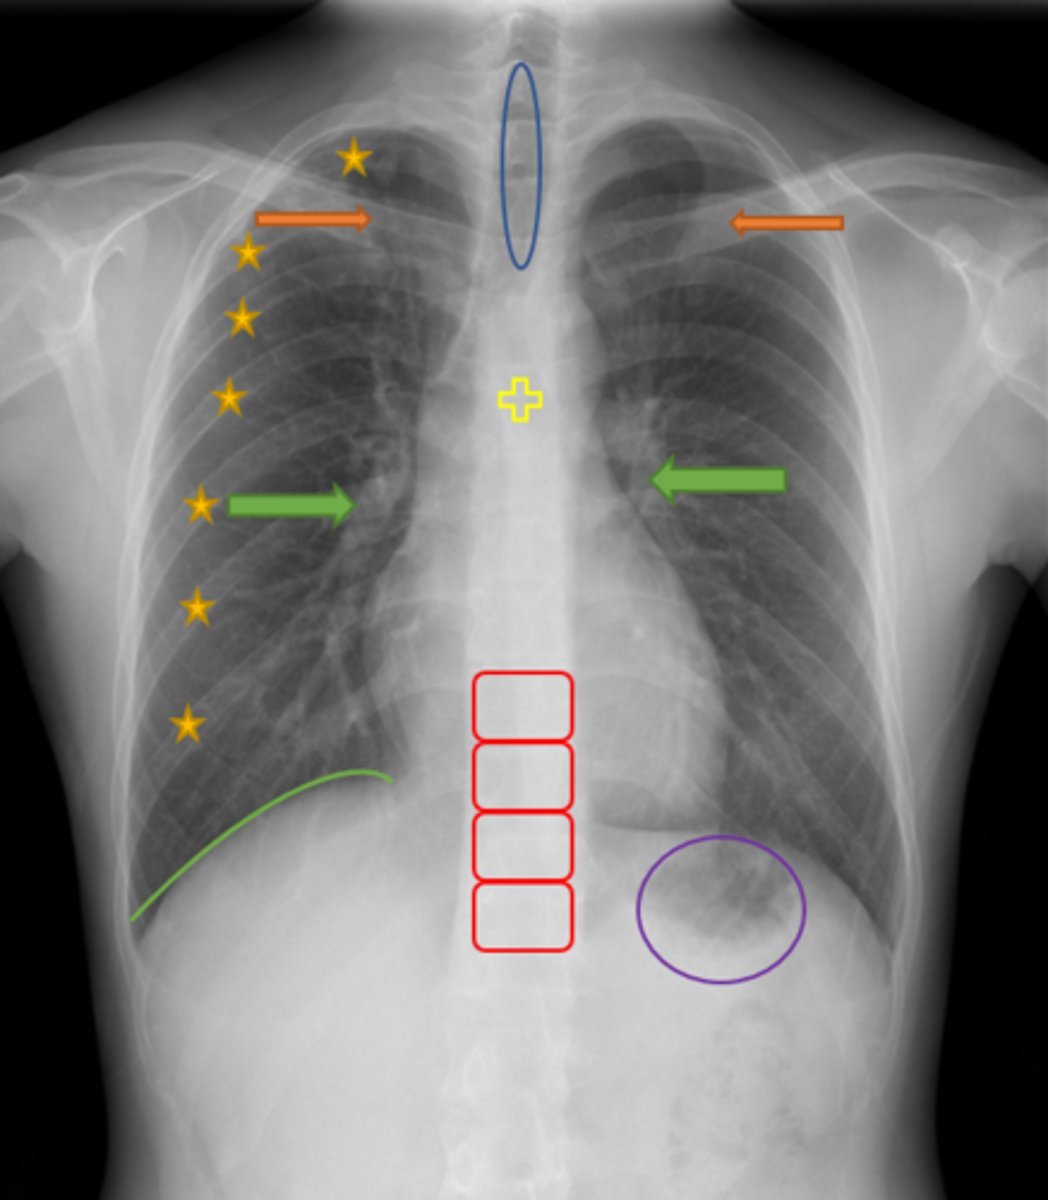

Trachea

Blue Oval

Pulmonary arteries

Green Arrows

Vertebrae/spine

Red Blocks

Clavicle

Orange Arrows

Ribs

Yellow Stars

Diaphragm

Green Line

Gastric bubble/stomach

Purple Circle

Carina

Yellow Cross